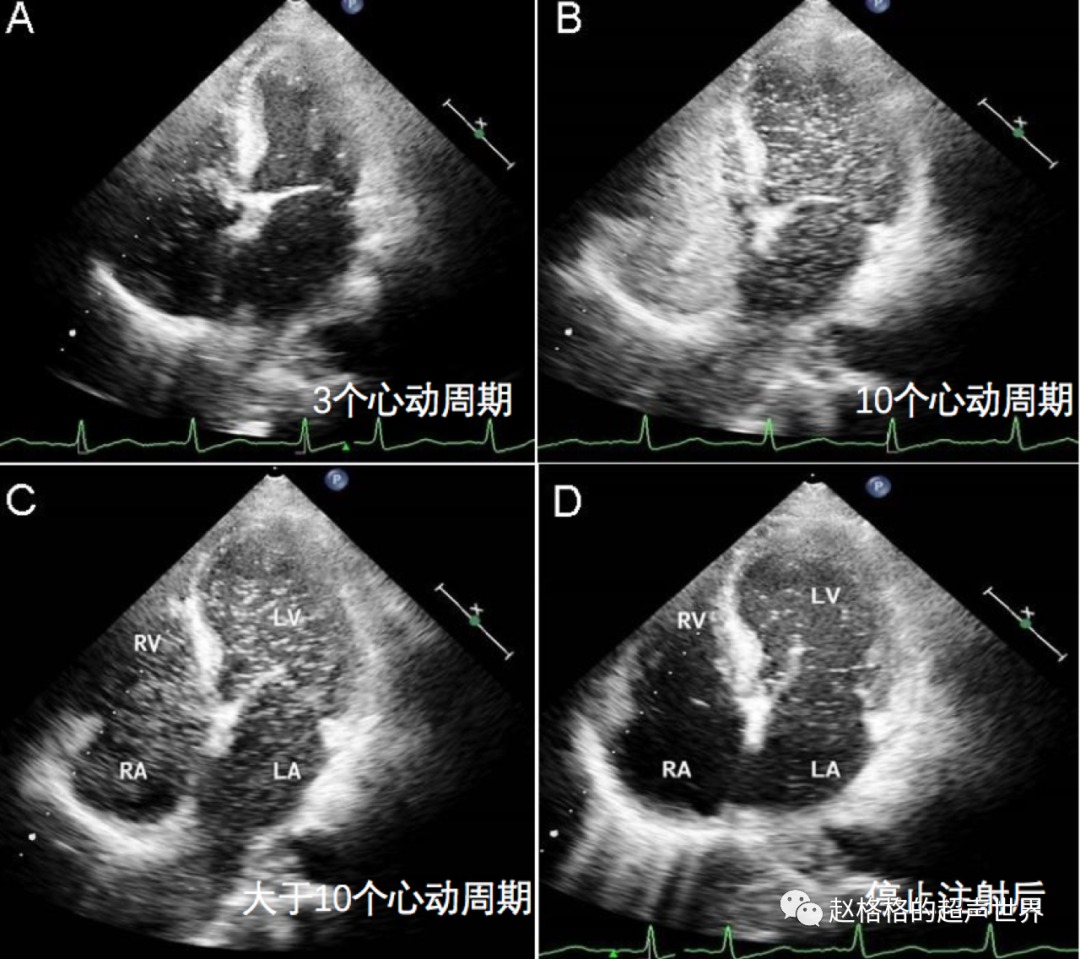

格格答:一般认为,左心显影迟于右心显影≤3个心动周期,多考虑为房水平分流,>6个心动周期多考虑存在肺动静脉水平分流,而在4~6个心动周期时二者均有可能。

这是一位60岁的肝硬化男子,胸痛,呼吸急促就诊,氧饱和度低,胸部X线和肺功能检查正常。

图A:在右心房和心室出现后,左心房中出现大量微气泡的延迟出现大于三个心动周期,这提示了肺动静脉瘘。

图B、图C:即使经过10个心动周期,左心室和右心室的微气泡密度也相同。

图D:停止注射后,左心室中出现微气泡,而右心室中没有气泡。